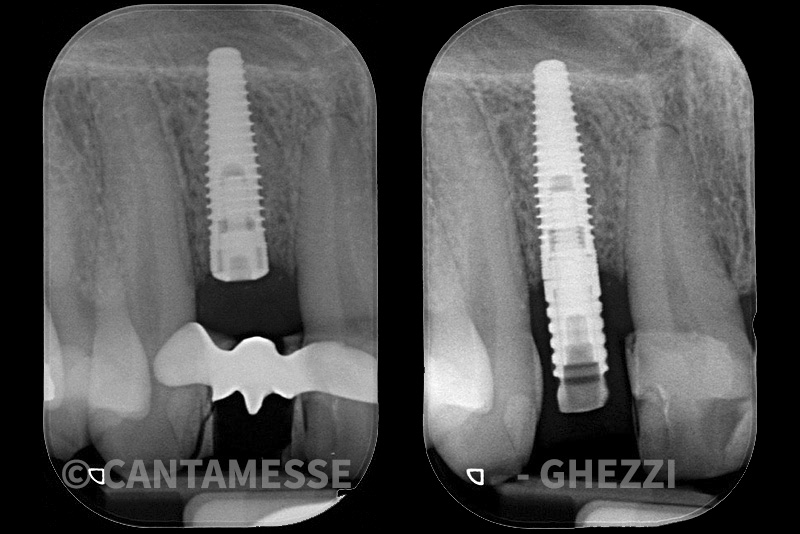

PREMESSA: in seguito all’estrazione dell’incisivo laterale superiore di destra, resasi necessaria per cause batteriche, si decide di affrontare il caso con il posizionamento di un impianto in sostituzione dell’elemento mancante dopo guarigione del sito infetto. Con tecniche rigenerative sia dei tessuti ossei mancanti a causa dell’infezione pregressa, sia dei tessuti gengivali che appaiono inizialmente troppo spostati in alto, si ripristina una corretta morfologia delle parabole (contorni) gengivali e delle papille interdentali (triangoli di gengiva tra due denti vicini).

Vengono utilizzati 2 tipi di provvisori: il primo, cementato ai denti vicini, viene utilizzato dal momento dell’estrazione del dente fino ad impianto osteointegrato (circa 6 mesi); il secondo, avvitato direttamente all’impianto, ha una funzione di prova estetica ma soprattutto di guida per la maturazione dei tessuti gengivali peri-implantari portandoli verso la maturazione completa prima di posizionare la corona finale in disilicato di litio.